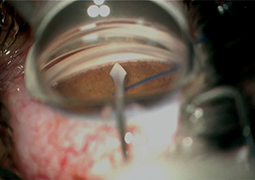

- Clinical Outcomes of Preserflo MicroShunt versus Trabeculectomy: A Retrospective 6-Month Study